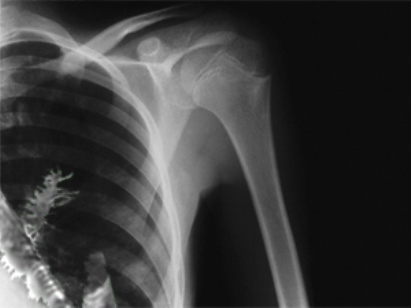

طول شاخه صنوبر حدود 5 سانتی متر بود. احتمالا دانه آن در اثر تنفس داخل ریه آرتیوم شده و بدن آرتیوم نتوانسته آن را دفع یا جذب کند و صنوبر با استفاده از محیط گرم و مرطوب ریه آرتیوم رشد کرده و به تدریج سبب بروز علائم درد و خلط خونی شده است.